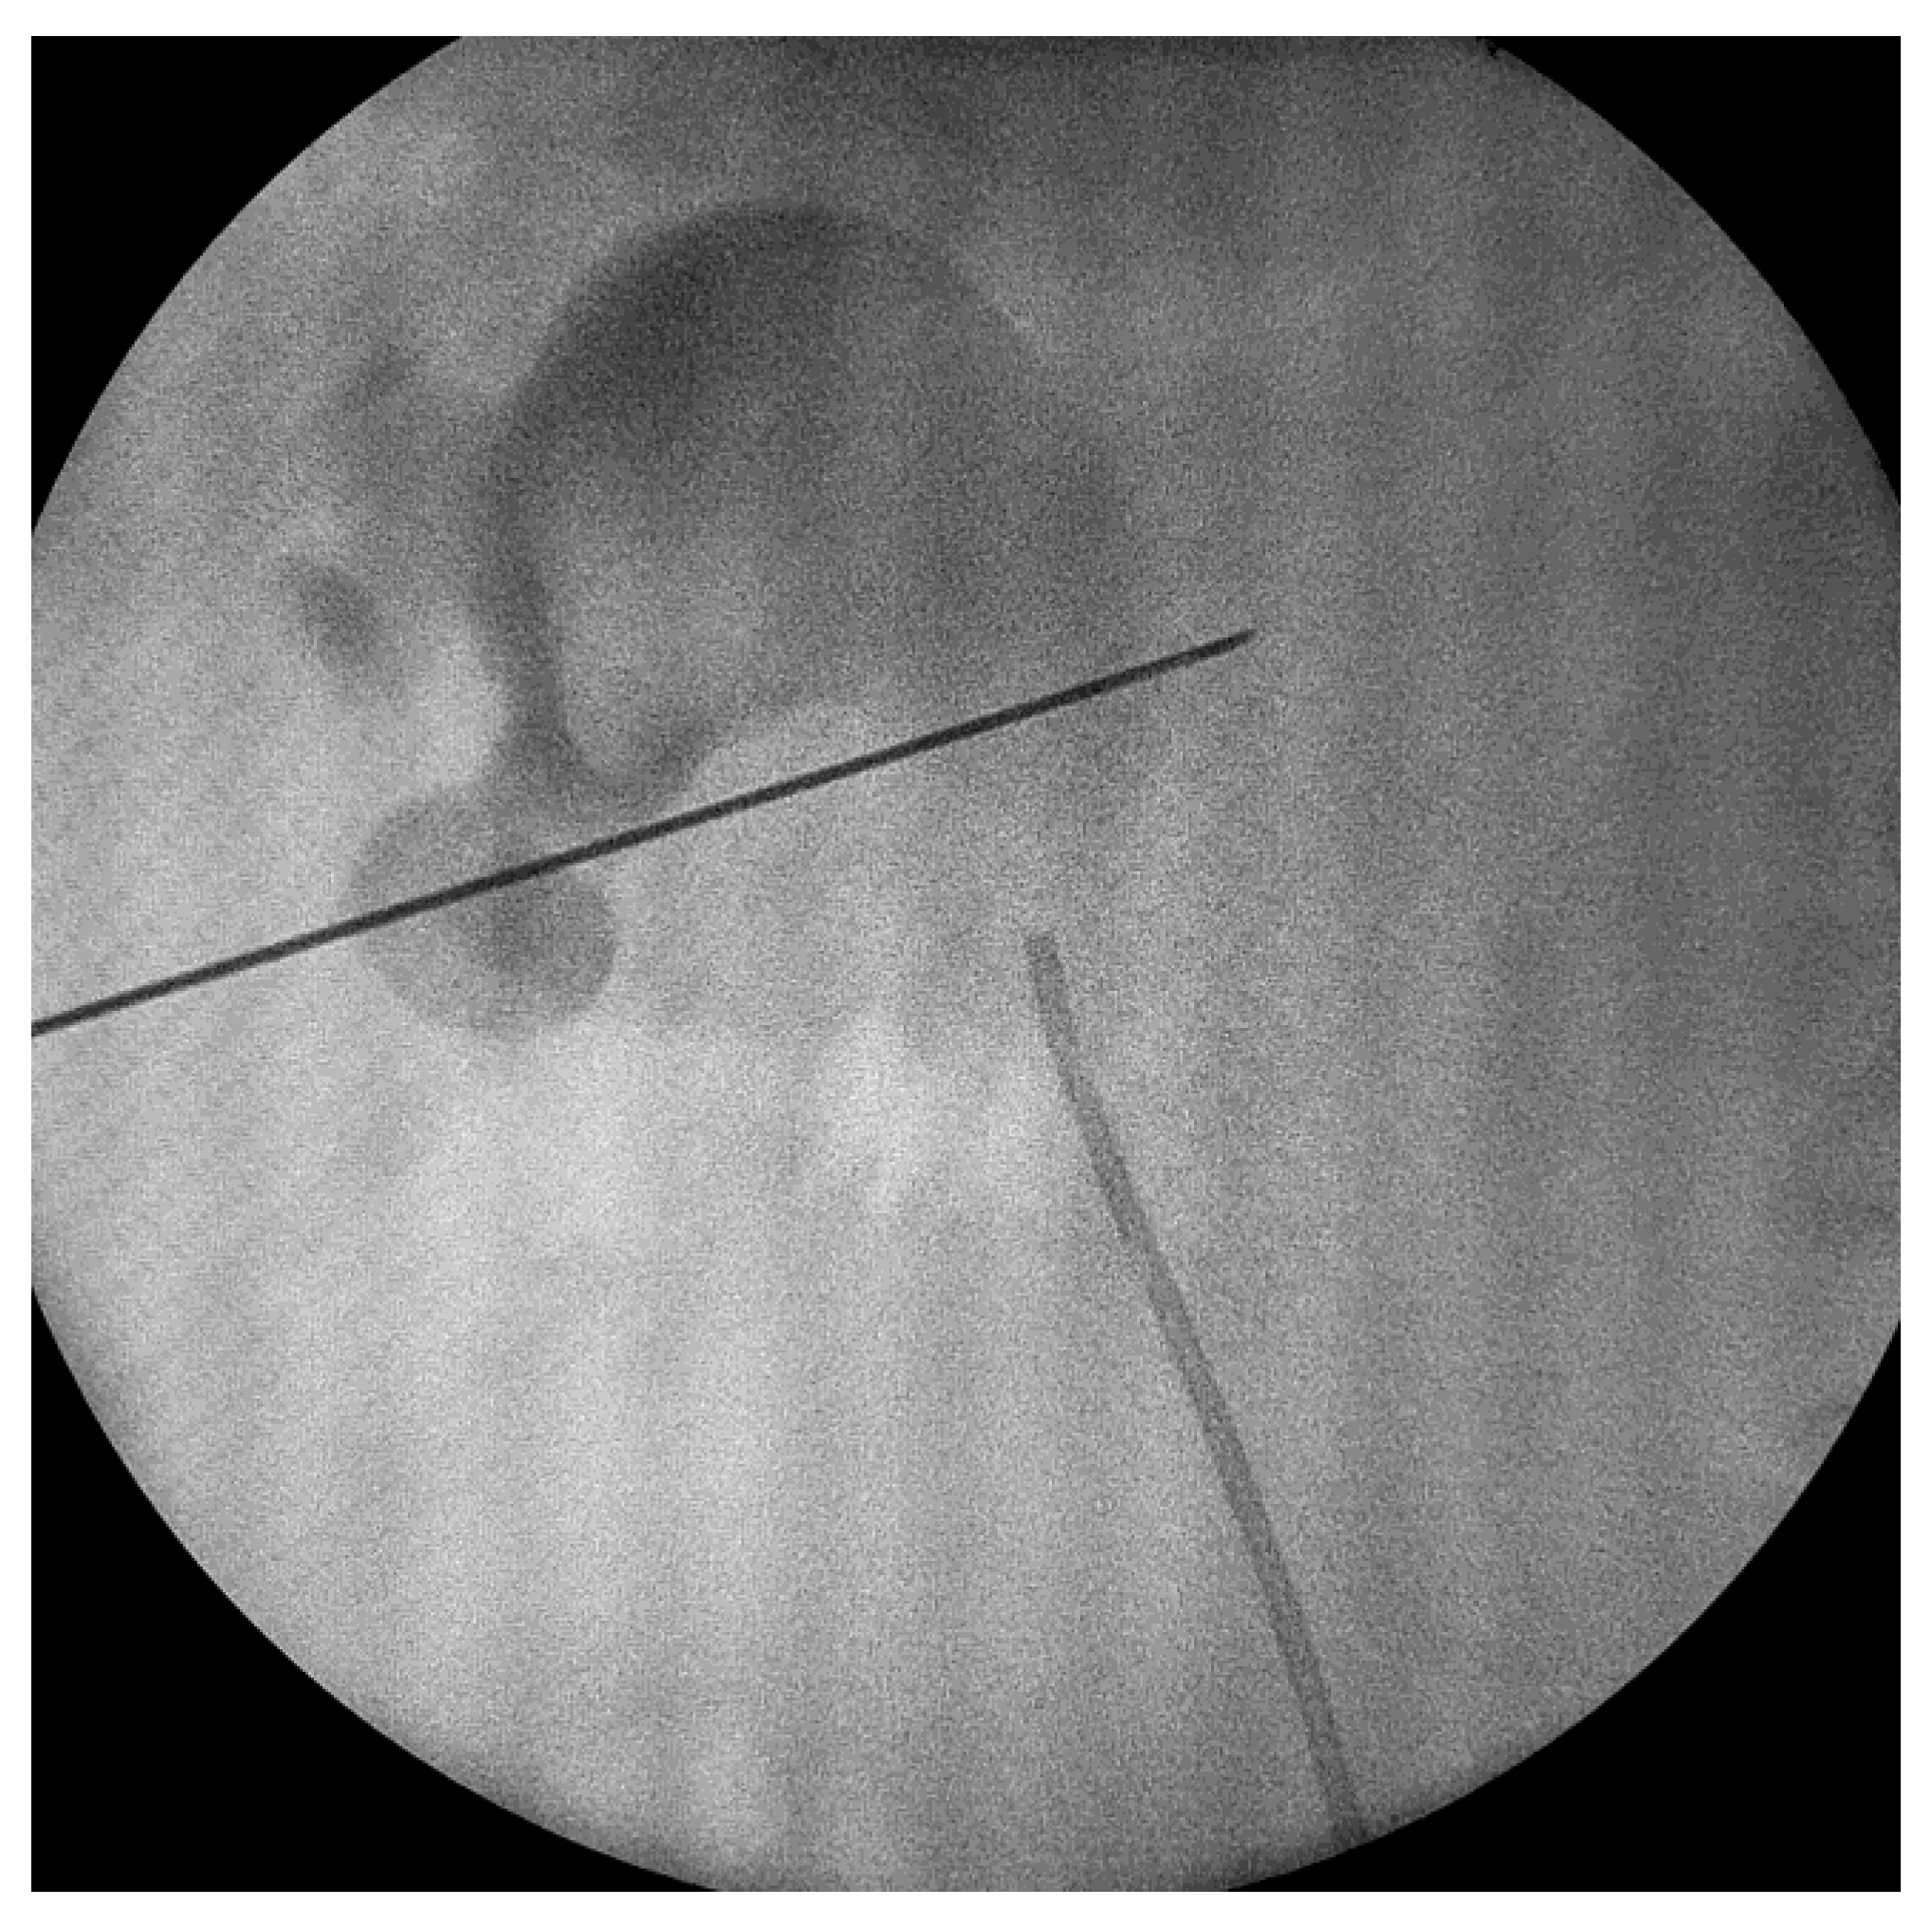

After that, a 0.035-inch hydrophilic guide wire was inserted into the collecting system. Dilation was performed using Amplatz dilators, and a 16 Fr Amplatz sheath was inserted. We used a 15.9 F rigid nephroscope and stone fragmentation was performed using Ho-YaG laser lithotripsy (350 or 550 μm fiber), ballistic energy or combined ultrasonic and ballistic lithotripsy (Figure 1 and Figure 2). Stone fragments were removed in the next step using the so called “vacuum effect” or using grasping forceps. The “vacuum effect” is based on a hydro-dynamic phenomenon which takes place during low-pressure, continuous-flow PCNL. Stone fragments located in line with the irrigation channel of the nephroscope were washed by the flow of water [10,11]. Some fragments were not removed with this technique so they needed extraction using a 1.9 F stone basket or tri-radiate graspers. After all fragments were removed, the collecting system was inspected visually and then evaluated with a contrast medium, under fluoroscopy, in order to identify residual stones and fragments or perforations.

Figure 2. Percutaneous renal access.